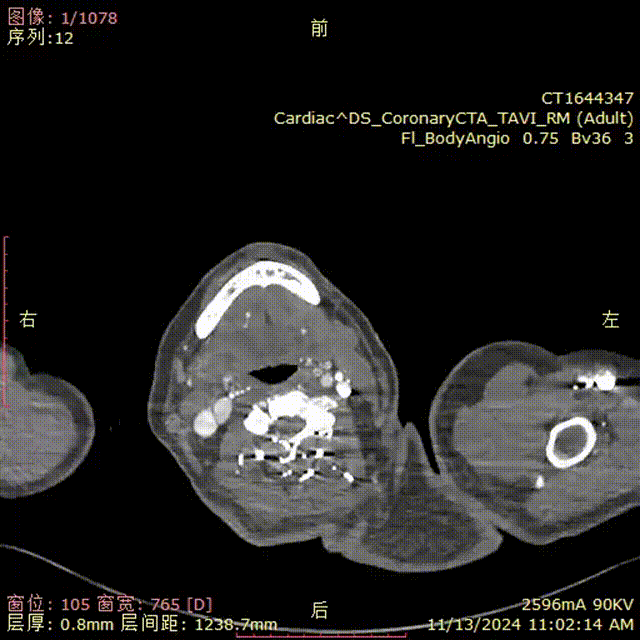

患者入院后行CTA检查,CTA提示患者为A型主动脉夹层。弓上三根分支血管及内脏区分支血管均发自真腔,夹层远端累及至髂总动脉。

gore医疗怎么样「胸有乾坤」强弓硬弩 一蹴而就——CTAG弓上三开窗治疗主动脉夹层病例报道_https://www.jmylbn.com_新闻资讯_第6张

术前CTA.